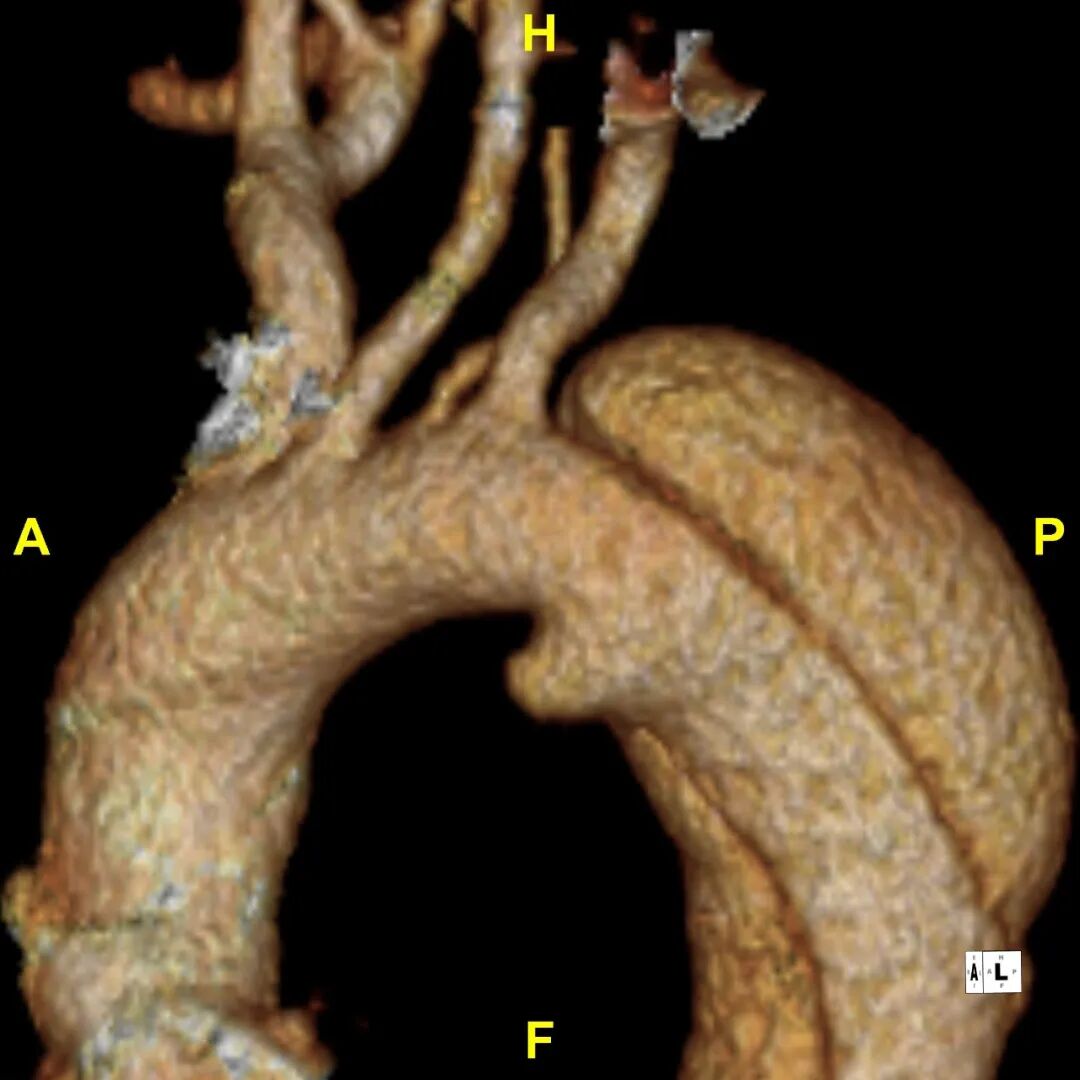

病例2

患者 10月前因“梗阻性黄疸、胆总管结石”检查发现主动脉夹层B型,否认腹痛、腰背痛,追问病史,2019年曾出现胸痛,行冠脉造影未见异常,当时血压170mmHg。诊断为:B型主动脉夹层累及到LSA后缘,左侧椎动脉发自于主动脉弓上的变异解剖形态

3.术前VS术后(3D影像)

gore医疗怎么样「胸有乾坤」释半功倍 得心应手——GORE®TAG® 可主动调控胸主动脉覆膜支架治疗B型主动脉夹层病例分享 复旦大学附属中山医院_https://www.jmylbn.com_新闻资讯_第16张

gore医疗怎么样「胸有乾坤」释半功倍 得心应手——GORE®TAG® 可主动调控胸主动脉覆膜支架治疗B型主动脉夹层病例分享 复旦大学附属中山医院_https://www.jmylbn.com_新闻资讯_第17张